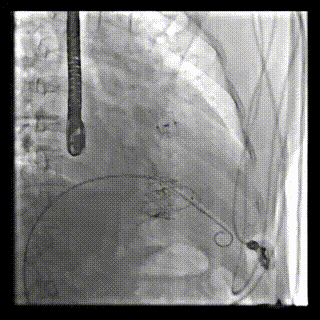

本周三例接受LuX-Valve Plus經血管三尖瓣置換術的患者中,第一例患者為冠狀動脈旁路移植術+Bentall+二尖瓣成形術后;第二例患者為永久起搏器植入術后,存在跨三尖瓣導線;第三例患者合并房顫、房缺及左心耳封堵術后。

三例患者入院后,葛均波院士團隊周達新教授、潘文志教授、張源博士、陳莎莎博士及心超室的潘翠珍教授、李偉教授對患者的情況進行詳細評估和討論,最終決定為三例患者選擇LuX-Valve Plus40mm、50mm和50mm型號的瓣膜進行手術治療。手術后即刻拔除氣管插管,術后患者三尖瓣反流癥狀得到顯著改善,復查心超結果顯示人工三尖瓣瓣膜支架固定穩(wěn)定,瓣葉關閉形態(tài)未見異常,未見明顯反流。